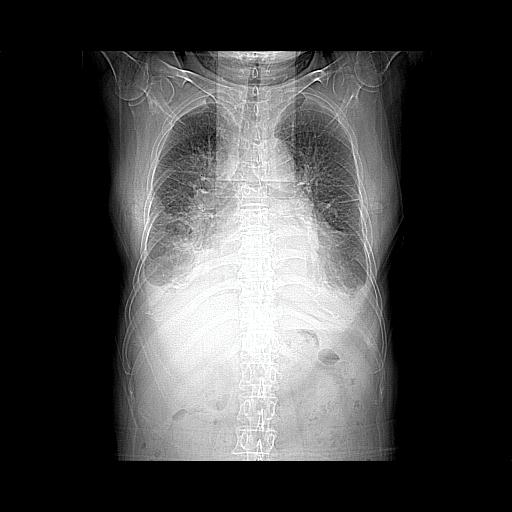

以下是引用jiangjing在2008-4-20 10:43:00的发言:[br]结合病史支持 冠心病[冠状动脉钙化],心功能不全,肺淤血、肺水肿,双侧胸腔与斜裂积液

以下是引用liuyue在2008-4-19 22:25:00的发言:[br]先考虑:1.心衰伴肺水肿、双侧胸腔积液、叶间积液、双下肺不完全性肺不张; [br] 2.冠状动脉粥样硬化。